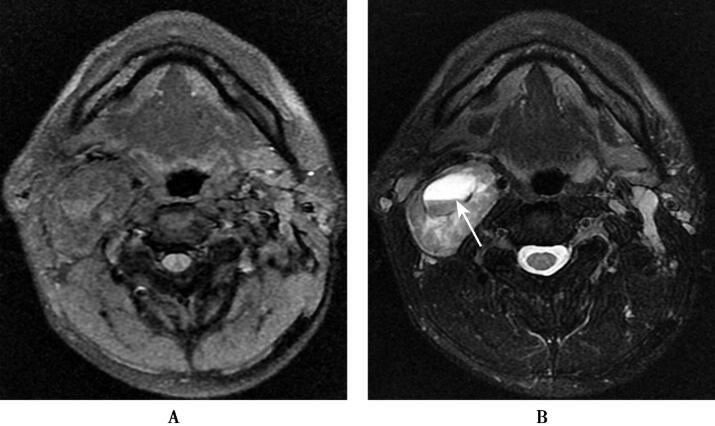

应用3.0T超导型MRI扫描仪(HDx,GE)8通道头颈联合线圈,获得SE联合脂肪抑制或水抑制成像体轴横断位T1 WI(TR/TE=2003.64ms/25.9ms,TI=860ms),5mm层厚,1mm间隔,512×512矩阵,220mm视野,横断位FSE加脂肪抑制T1WI(TR/TE=3660ms/103.25ms),3mm层厚,1mm间隔,512×512矩阵,180mm视野。DWI:b=1000s/mm2,TR=5400ms,TE=75.2ms,220mm视野,5mm层厚,1mm间隔。应用钆喷酸葡胺(剂量0.1mmol/kg体重),以2.5ml/s流率注射完成增强扫描,获取横断位、冠状位和矢状位SE的T1WI(图1)。

图1右侧颈动脉间隙神经鞘瘤

1.右侧颈动脉间隙神经鞘瘤右侧口咽旁间隙有一个卵圆形异常信号,瘤周有包膜,T1WI呈等或稍高信号,T2WI上呈稍高混杂信号,病灶内部有囊变,增强扫描病灶实性部分显著强化,中央囊变区无强化。

2.神经纤维瘤肿瘤的发生部位、肿瘤信号强度、强化表现均与神经鞘瘤相似,但神经纤维瘤无包膜,很少发生囊变和坏死。

3.颈动脉体瘤肿瘤表现为T1WI低信号,T2WI高信号。肿瘤内部可见多发蜿蜒迂曲和(或)点状血管流空信号为其特征性表现,增强扫描病灶显著强化。肿瘤部分或全部包绕邻近颈内、外动脉。

4.颈动脉间隙淋巴结转移瘤可发生在颈动脉间隙,肿大淋巴结内部可出现坏死。但淋巴结转移瘤一般为颈部多发,增强扫描病灶呈轻、中度强化。

颈动脉间隙神经鞘瘤为起源于第9~12对脑神经施万细胞的良性肿瘤,常呈梭形或卵圆形,沿神经走行方向呈纵向生长。本病可累及任何年龄人群,以成年人多见,其临床病程较长,主要表现是颈外侧部肿块,边缘光滑,边界清楚。病理上肿瘤主要由Antoni A区和B区组成,前者细胞呈梭形,排列紧密,在T1WI呈等或低信号,T2WI为等或高信号,增强扫描病灶显著强化;后者细胞少,排列稀疏,呈网格样,细胞间有较多液体,位于肿瘤囊变区,在T1WI呈明显低信号,T2WI呈明显高信号,增强扫描无强化。因神经鞘瘤多来自迷走神经,通常将颈内静脉向后外侧推移,颈内动脉向前内侧推移,血管受压变窄。